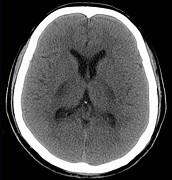

问题 男,57岁,头痛、头晕1周,言语不清,饮水呛咳两天,既往有鼻咽癌病史,给予放射治疗,CT检查如图所示,最可能的诊断为()

选项 A.脱髓鞘病变 B.脑炎 C.放射性脑病 D.脑梗死 E.胶质瘤

答案 C